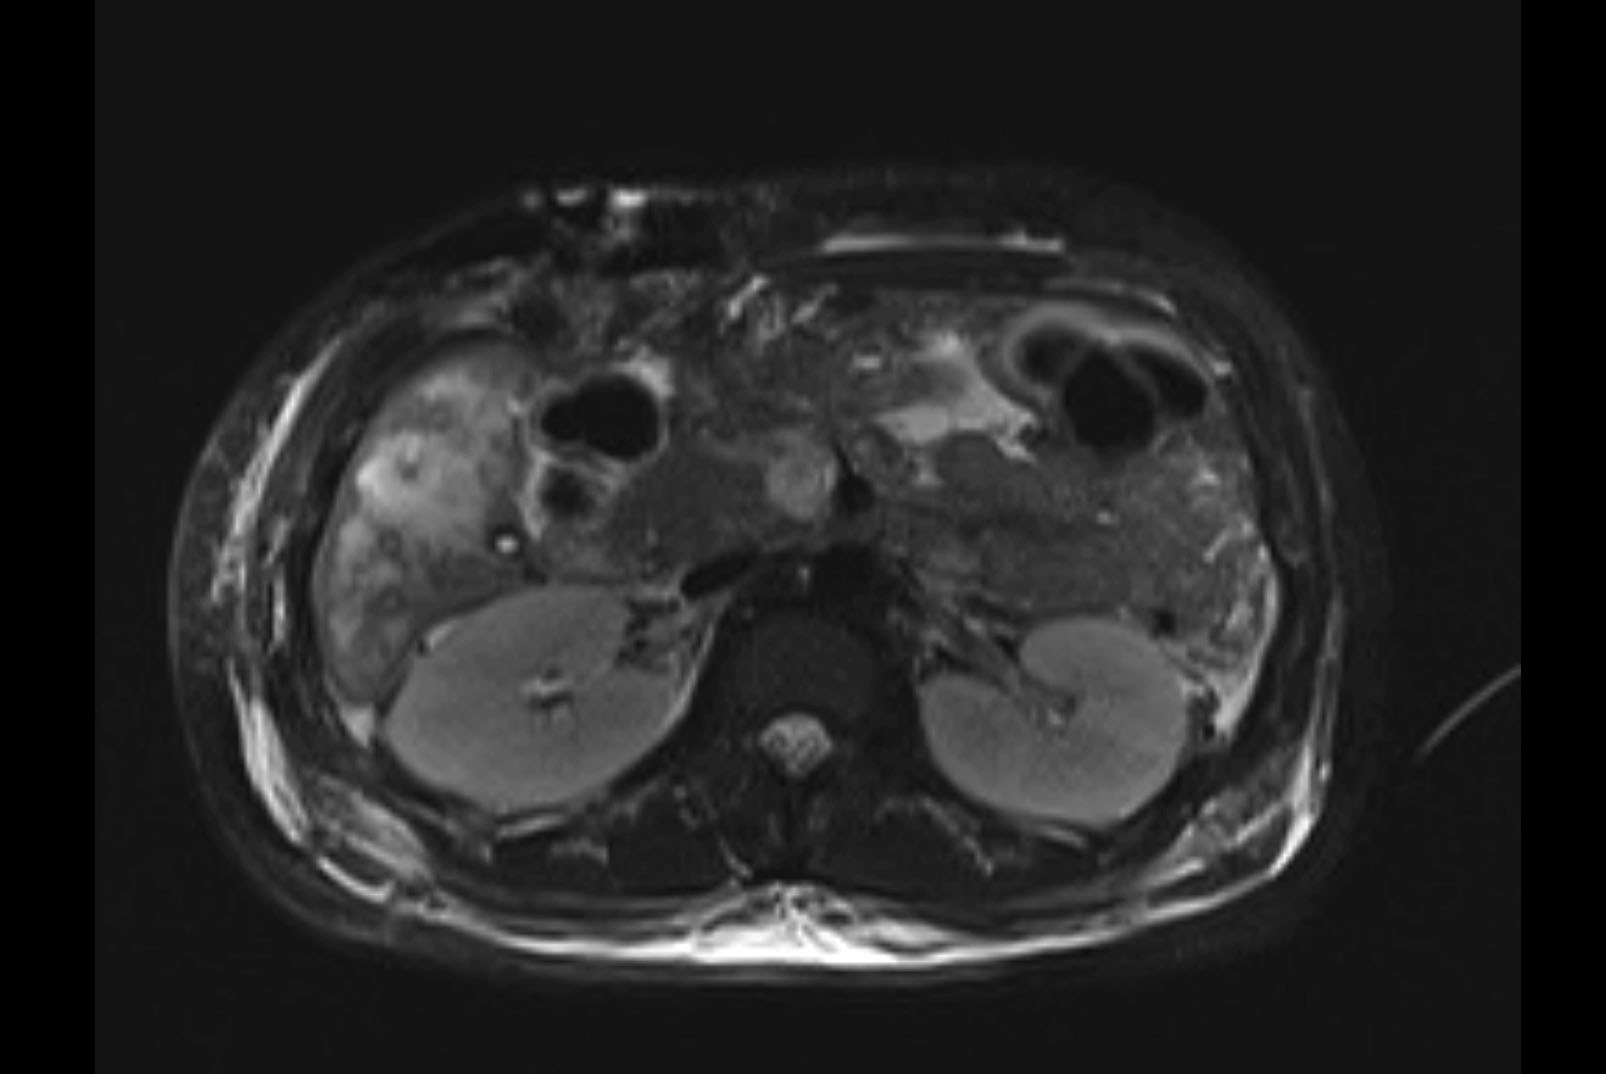

Imaging Analysis

Look through the patient's CT scan to identify any areas of concern for the necessary procedure.

MRI T2

Based on initial findings, which issue(s) would you be most concerned about?